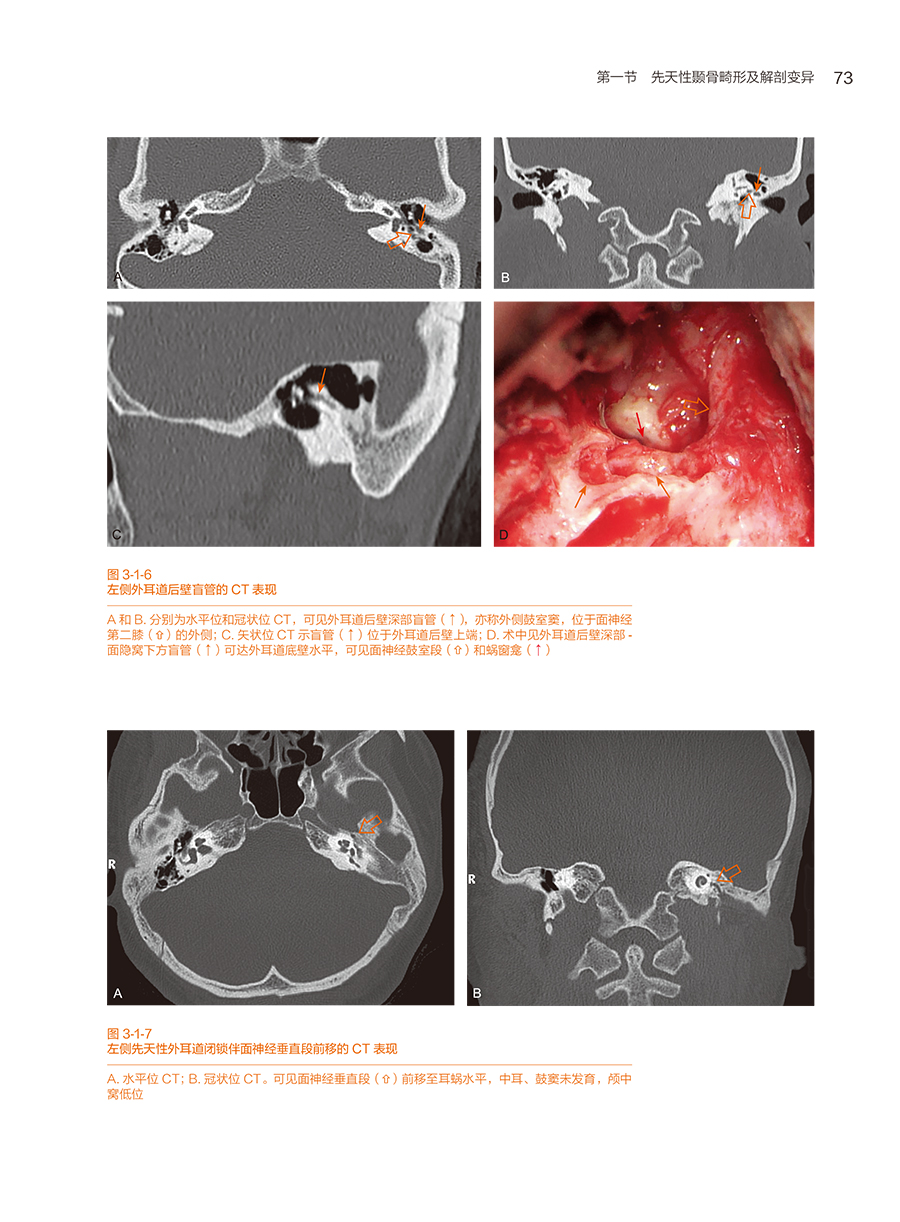

第一节 先天性颞骨畸形及解剖变异

一、先天性外耳道闭锁(或狭窄)伴中耳畸形及术后并发症